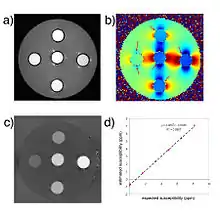

Quantification of contrast agent

For exogenous susceptibility sources, the susceptibility value is theoretically linearly proportional to the concentration of the contrast agent. This provides a new way for in vivo quantification of gadolinium or SPIO concentrations.[20]